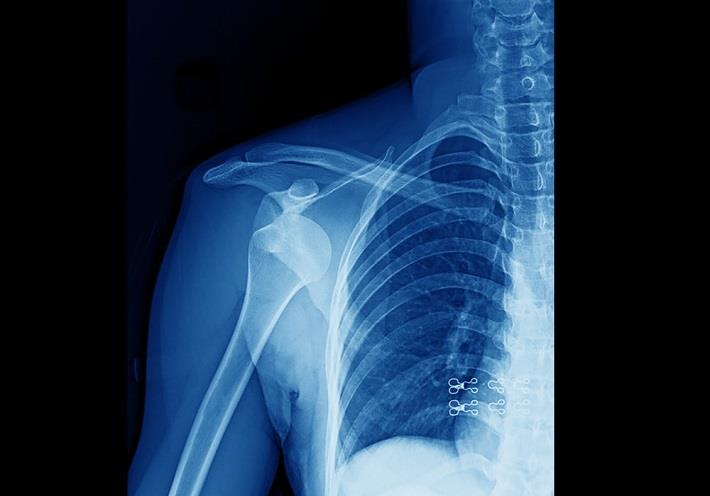

עם ההגעה למרפאה או לבית החולים, האזור הפגוע ייבדק על ידי רופא/ה מתחום האורתופדיה. המטרה בבדיקה היא לבחון את זרימת הדם לאזור, עיוות באזור והאם העור נפגע גם הוא. במידה וקיים חשש לשבר או לנקע, יהיה צורך בצילום רנטגן. לעיתים, ייתכן שתידרש בדיקת הדמיה אחרת כגון MRI. מטרתן של בדיקות אלו הן לאפשר לראות בדיוק מה קורה במפרק או בעצמות המעורבים בפריקה[5].